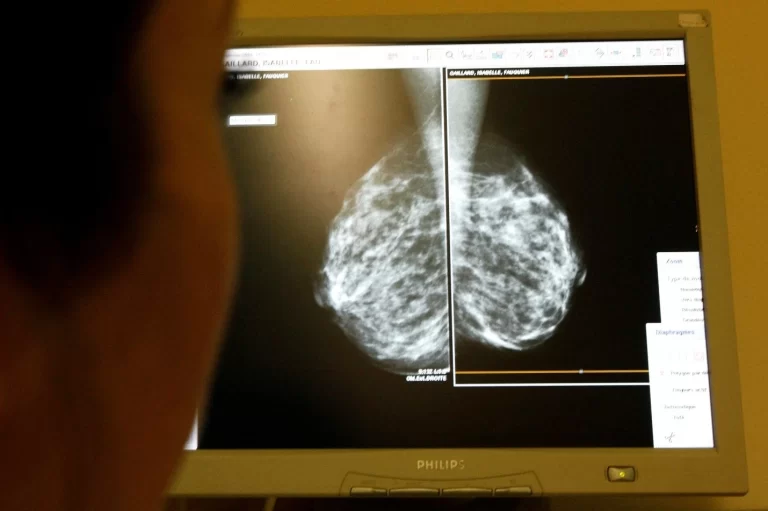

لزوم غربالگری سرطان پستان برای زنان در معرض خطر متوسط از ۴۰ سالگی

کارگروه خدمات پیشگیرانه آمریکا (USPSTF) اعلام کرد زنانی که در معرض خطر متوسط ابتلا به سرطان پستان قرار دارند باید از ۴۰ سالگی هر سال ماموگرافی غربالگری انجام دهند و پوشش بیمهای برای ماموگرافی این گروه سنی طبق قانون تقویت شود.